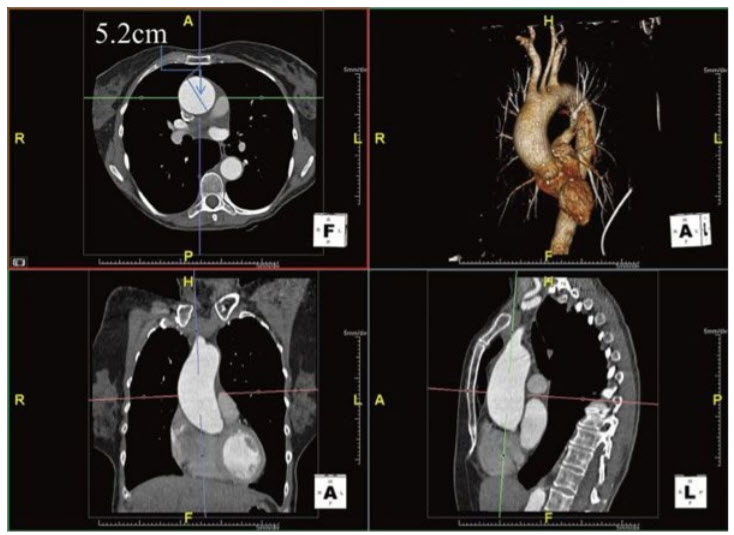

The patient undergoes a gated computed tomography angiography of the thorax (Fig. below).